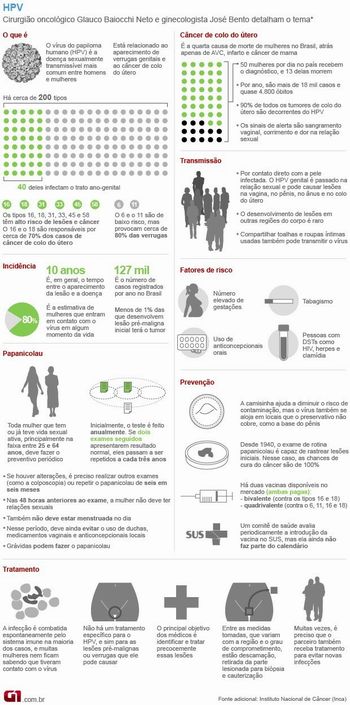

Tema 6 - Vírus HPV e neoplasias

-

HPV e câncer. Disponível em: http://www1.inca.gov.br/conteudo_view.asp?id=2687. Acessado em 16/05/2013.

- Dois terços das mulheres não ligam HPV a câncer, diz estudo. Disponível em: http://g1.globo.com/bemestar/noticia/2013/05/dois-tercos-das-mulheres-nao-ligam-hpv-cancer-diz-estudo.html. Acessado em 16/05/2013.

- Anvisa indica vacina de HPV para prevenir também o câncer anal. Disponível em:http://g1.globo.com/bemestar/noticia/2013/01/anvisa-indica-vacina-de-hpv-para-prevenir-tambem-o-cancer-anal.html. Acessado em 16/05/2013.

- HPV pode causar verrugas genitais e câncer de colo do útero ou de pênis. Disponível em: http://g1.globo.com/bemestar/noticia/2012/01/hpv-pode-causar-verrugas-genitais-e-cancer-de-colo-do-utero-ou-de-penis.html. Acessado em 16/05/2013.

- Vírus do HPV e da hepatite podem causar câncer, mas têm prevenção. Disponível em: http://g1.globo.com/bemestar/noticia/2012/10/virus-do-hpv-e-da-hepatite-podem-causar-cancer-mas-tem-prevencao.html. Acessado em 16/05/2013.

-

Câncer de boca, garganta e ânus por HPV cresce nos EUA, aponta relatório. Disponível em: http://g1.globo.com/bemestar/noticia/2013/01/cancer-de-boca-garganta-e-anus-por-hpv-cresce-nos-eua-aponta-relatorio.html. Acessado em 15/05/2013.

Fonte da imagem: http://g1.globo.com/bemestar/noticia/2013/01/anvisa-indica-vacina-de-hpv-para-prevenir-tambem-o-cancer-anal.html. Acessado em 16/05/2013.